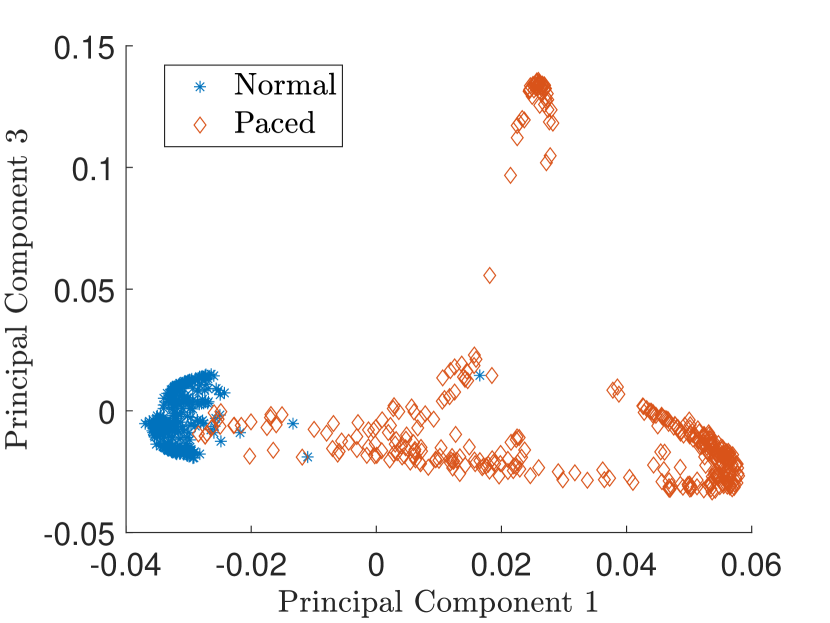

In Fig. 9 the latent feature space projected on the first two principal components is shown. Kernel PCA is also able to separate between the normal and paced beats.

Fig. 10 shows the result in input space of moving along the first principal components in the latent feature space. As original base point we take a normal beat signal, i.e. corresponding to a hidden unit on the bottom right of Fig. 9(a). The smooth transition between the beat patterns allows for interpretation of the first principal components. This allows a clinical expert to understand on what basis the paced beats are separated by the principal components and if this basis has a physiological meaning. In order to investigate the separated region of the latent space at the top of Fig. 9(b) we start from a paced beat pattern and vary along the third principal component. This allows us to see which sort of heartbeat patterns are responsible for this specific distribution in the latent space.